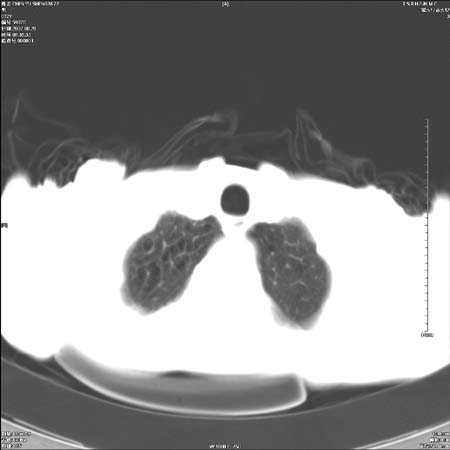

男性,72岁,既往肺结核,今复查。无前片对比。

纵隔窗

右侧中央型肺癌伴中叶不张可能性大,建议增强扫描.右上肺陈旧性肺结核.慢性支气管炎伴肺气肿.右侧少量胸腔积液.

右侧中央型肺癌伴中叶不张可能性大,建议纤支镜检查.右上肺陈旧性肺结核.肺气肿。

典型右肺中心型肺癌

右侧中央型肺癌伴肺不张可能性大,建议增强扫描.右上肺陈旧性肺结核.慢性支气管炎伴肺气肿.右侧少量胸腔积液.

右肺中心型肺癌

右侧中央型肺癌.上肺陈旧性肺结核.

1右侧中央型肺癌伴中叶不张2右侧少量胸腔积液3右上肺陈旧性肺结核

1.右肺中心性肺癌并右肺中叶综合征2。右侧胸腔少量积液3。右肺上叶结核球已钙化,4。慢支伴肺气肿

右侧中央型肺癌伴中叶不张可能性大,建议纤支镜检查.右上肺陈旧性肺结核.肺气肿。

右侧中央型肺癌伴中叶不张可能性大,建议增强扫描.右上肺陈旧性肺结核.慢性支气管炎伴肺气肿.右侧少量胸腔积液.

右侧中央型肺癌伴中叶不张

右肺中央型肺癌伴右肺中叶不张。

右上肺陈旧性肺结核。

支持右肺中心型肺癌并中叶不张,右上肺陈旧性肺结核钙化,右侧少量胸腔积液。

支持右侧中央型肺癌伴中叶不张可能性大,建议增强扫描.右上肺陈旧性肺结核.慢性支气管炎伴肺气肿.右侧少量胸腔积液.

支持 1右侧中心型肺癌伴中叶不张2右侧少量胸腔积液3右上肺陈旧性肺结核4双肺局限性肺气肿

1,右侧中央型肺癌.

2,右上肺陈旧性肺结核.

1.右侧中央型肺癌伴中叶不张,建议纤支镜检查.

2.右上肺陈旧性肺结核.

3.肺气肿。

4.右侧少量胸腔积液.

右侧中央型肺癌伴中叶不张并纵隔淋巴结增大,建议增强扫描.右上肺陈旧性肺结核.慢性支气管炎伴肺气肿.右侧少量胸腔积液。

右肺中心型肺癌并肺不张,陈旧性肺tb.慢支,肺气肿.

陈旧性肺结核.慢性支气管炎伴肺气肿,中央型肺癌伴中叶不张。

右侧中央型肺癌伴中叶不张可能性大;右上肺陈旧性肺结核.慢性支气管炎伴肺气肿

陈旧性结核是存在,但真正致命的却是右侧中心型肺癌。